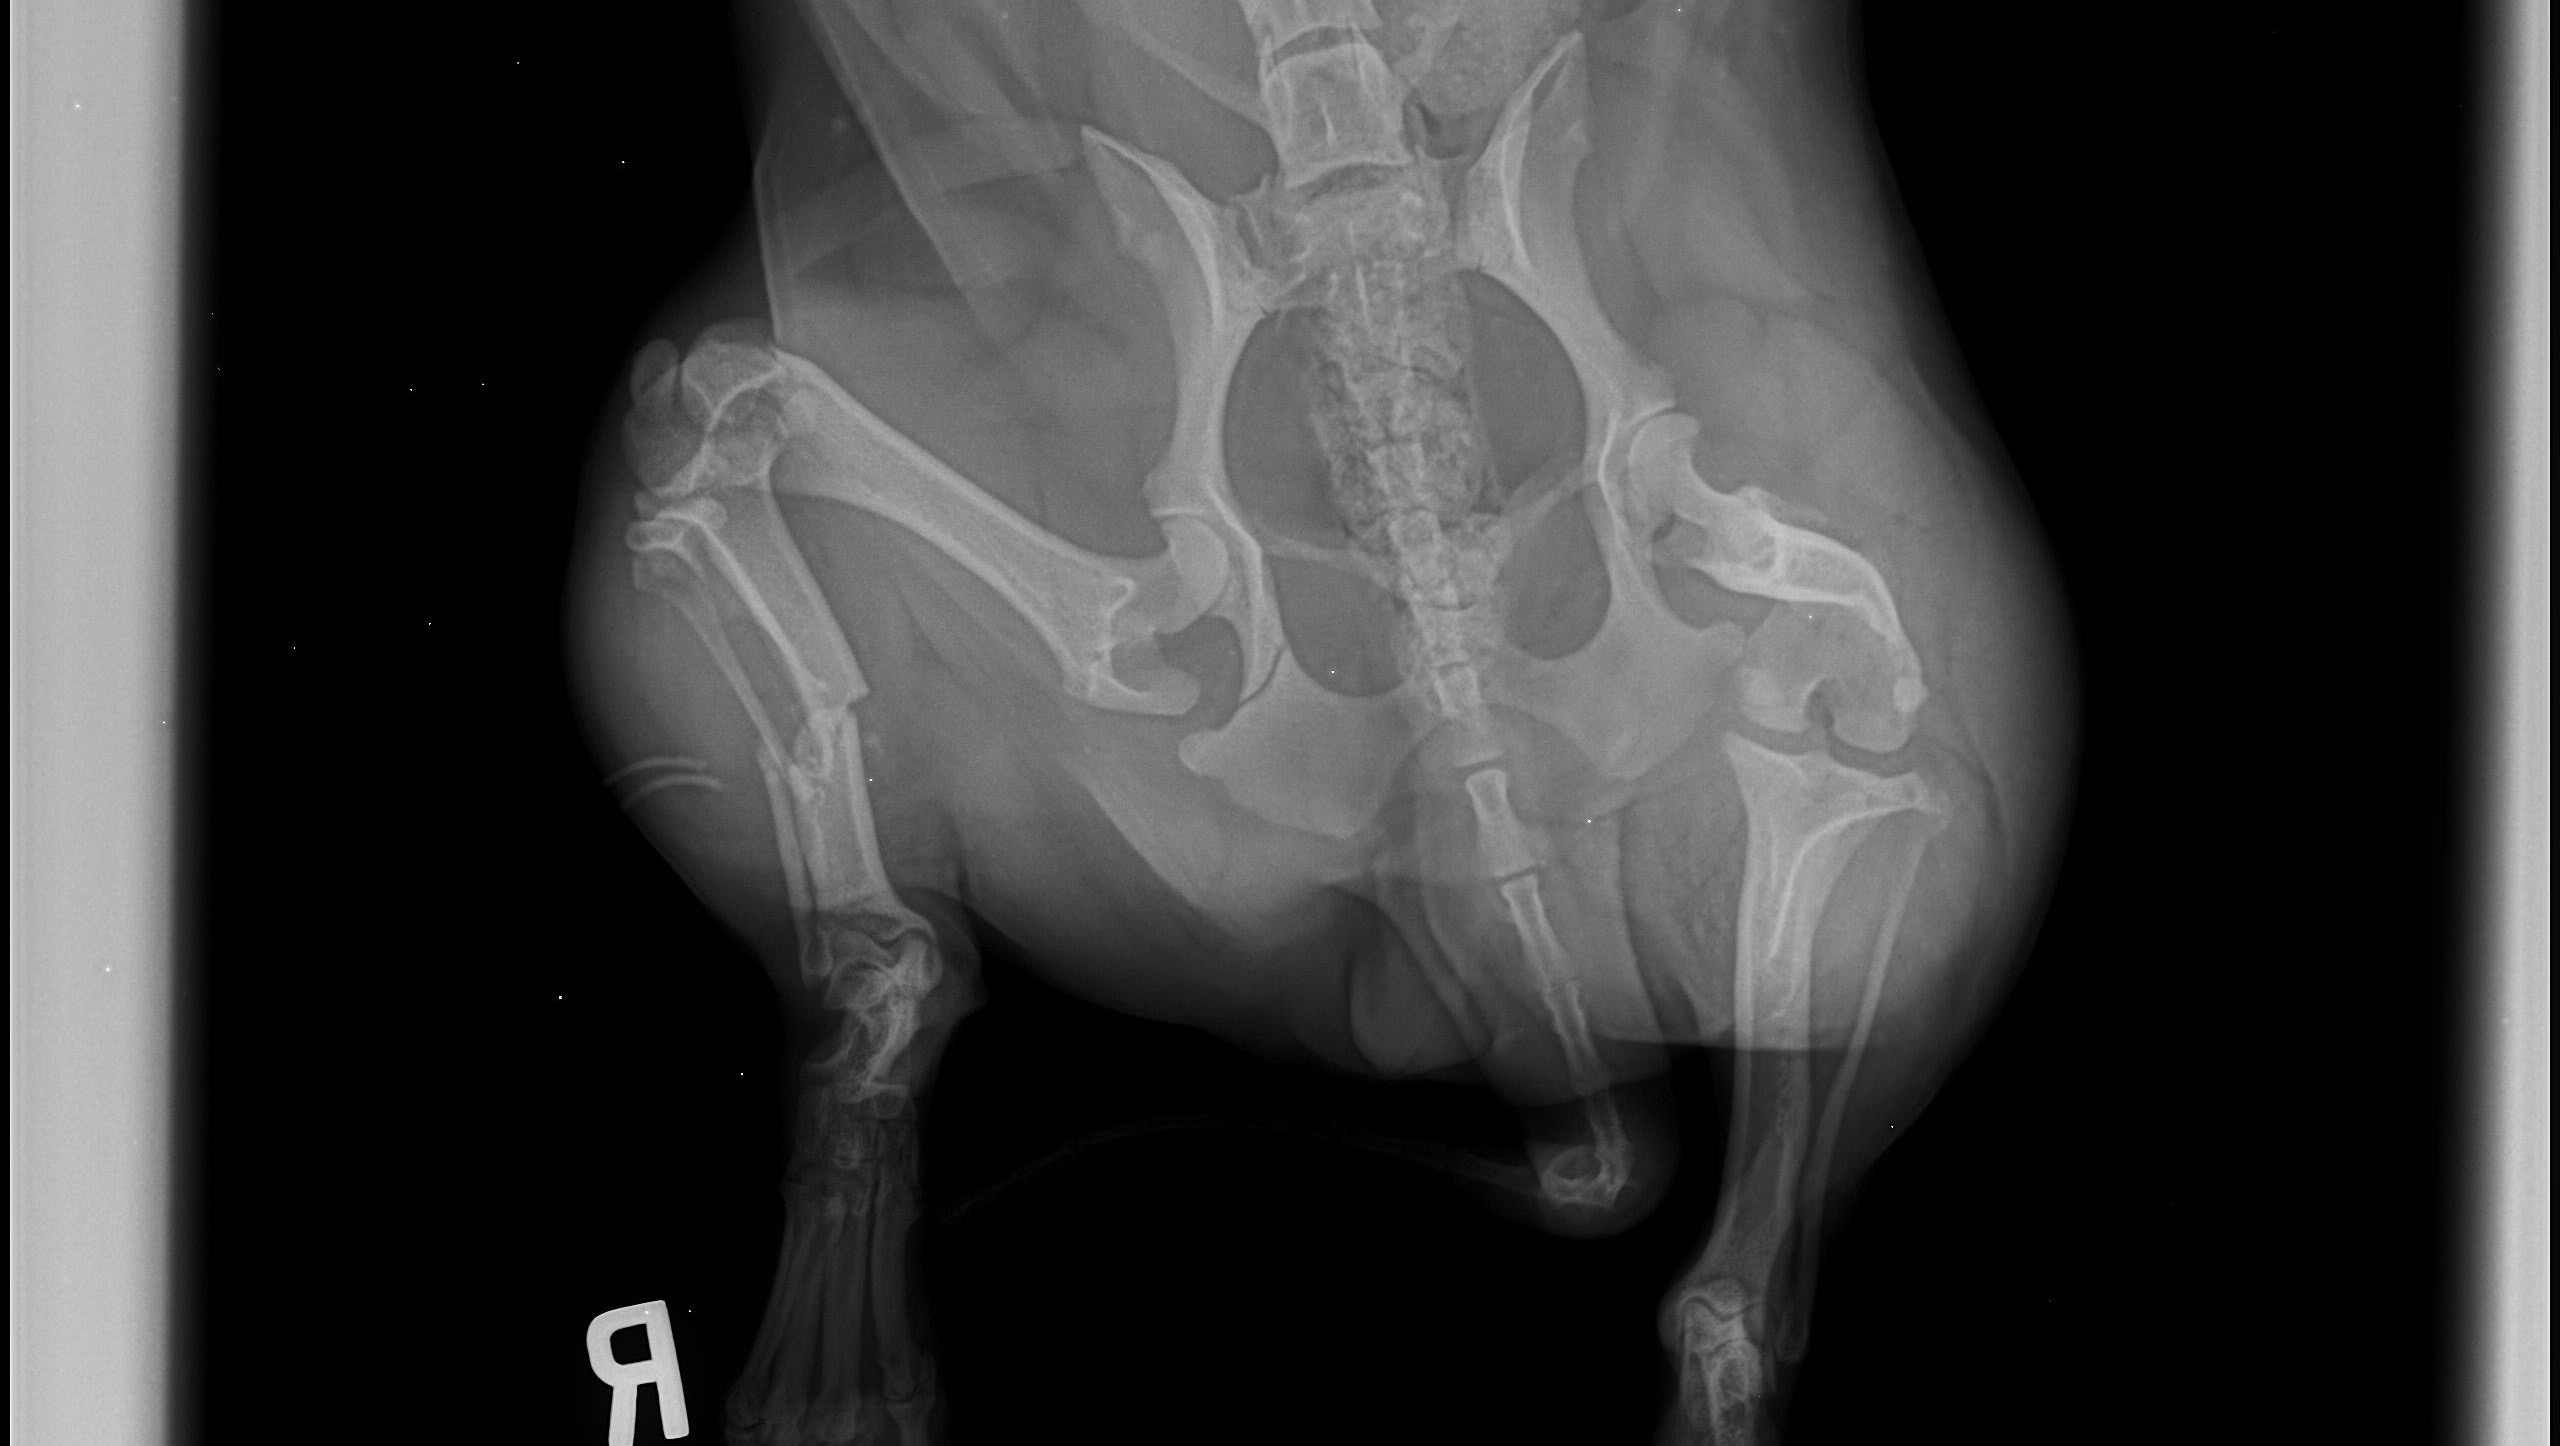

The dogs name is unknown, but we had to give her a name so we decided on Tulip temporarily. Tulip was taken to the veterinarian and we discovered she has a broken back leg and a small fracture in her hip. She will need surgery with external fixators to repair the leg. Her bloodwork is normal, she was checked for intestinal parasites and heart worms which were both negative. She does have some bruising on her leg and her back from debris falling on her but otherwise she is in good spirits.